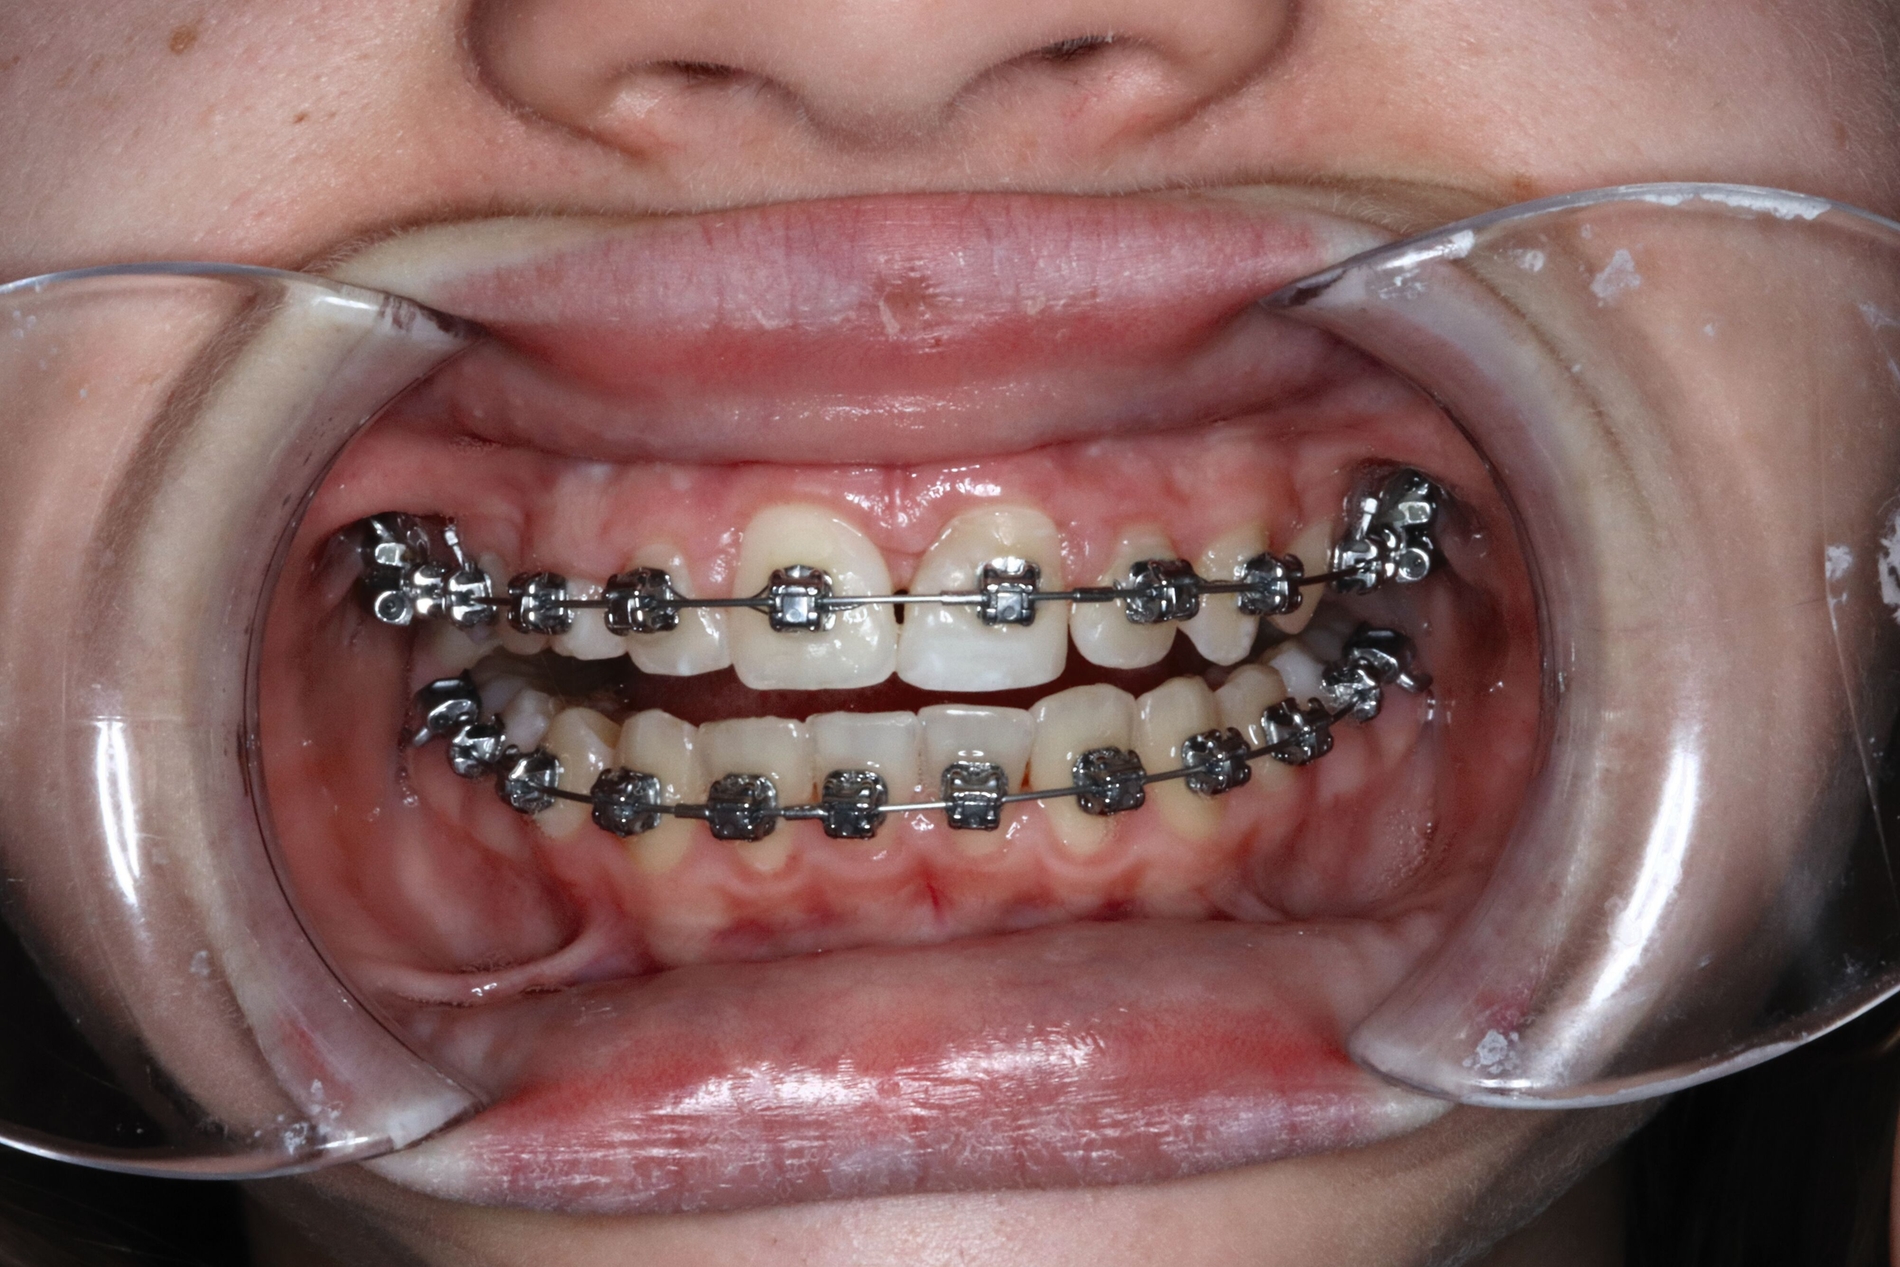

Auf Empfehlung des mitbehandelnden Kieferorthopäden sollte der natürliche Lückenschluss in regio 53 belassen und die autogene Transplantation des verlagerten Eckzahns 13 an die Stelle des verloren gegangenen Zahnes 21 durchgeführt werden. Der Eckzahn 13 wurde etwa einen Monat später in die Region 21 transplantiert und am zuvor eingebrachten kieferorthopädischen Bogen kunststoffadhäsiv fixiert (Abbildung 4).

Der spätere kunststoffadhäsive Aufbau des Zahnes erfolgte nach Erreichen des isogingivalen Niveaus im Vergleich zum Nachbarzahn 11 durch kieferorthopädische Extrusion (Abbildung 5).

Ein Jahr später präsentiert sich das Transplantat in regio 21 reizfrei und perfekt in Okklusion stehend. Die Transplantation des verlagerten Eckzahns an die Stelle des Zahnes 21 war mit einer ausgezeichneten Wiederherstellung der knöchernen und weichgewebigen Situation verbunden (Abbildung 5).